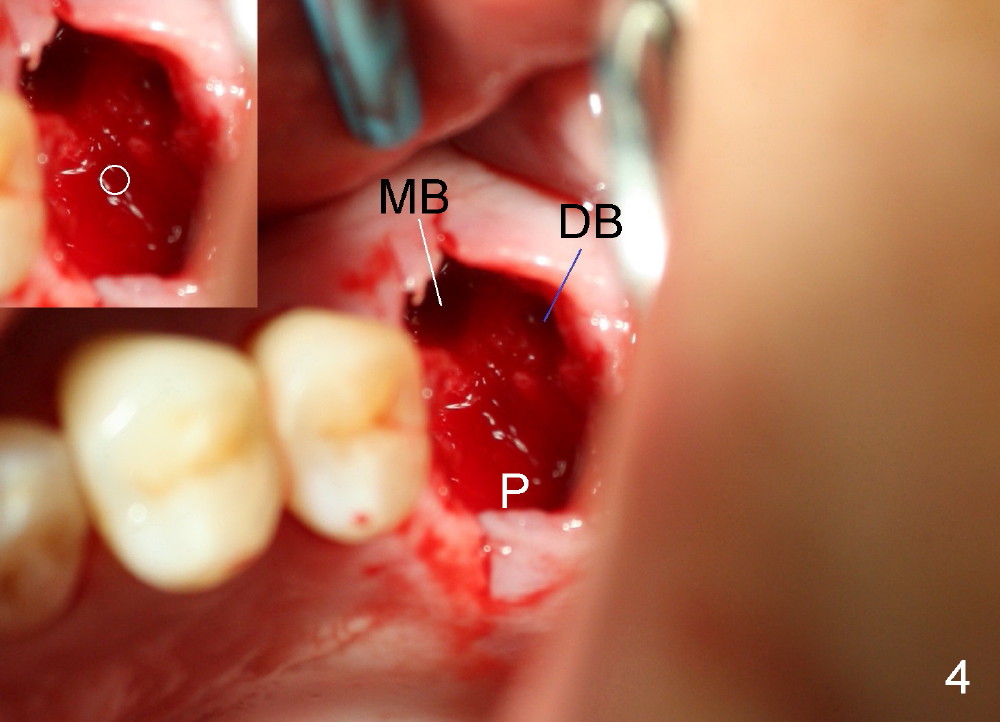

Bone density around the molars (including apical to #14) (Fig.1 black *) is higher than that around the premolar (white *). In fact the tooth has horizontal root fracture (Fig.2: <: CEJ), consistent with high bone density (strong mastication). An immediate implant is planned (Fig.3). After extraction, osteotomy starts at the buccal slope of the palatal (Fig.4 P) socket. Because of high bone density apical to the sockets, drills are required for osteotomy in the septum (type II bone) instead of osteotomes and primary stability is easily achievable (>60 Ncm). When a 7 mm implant (Fig.6 I)) is placed, the peri-implant gaps are much smaller (*) than that with a 4.5 mm tap (Fig.5 T). This helps bone grow faster toward implant. A long implant (17 mm) is necessary for this case to obtain primary stability in the apical one (double arrows in Fig.6). With reamers, a fair amount of autogenous bone is harvested during drilling, mixed with allograft and synthetic bone and placed in the remaining buccal (Fig.7) and palatal (Fig.8) sockets. The openings of the buccal and palatal sockets are covered with collagen dressing (C) and perio dressing. The latter is kept in place by a short abutment (Fig.6-8 A).